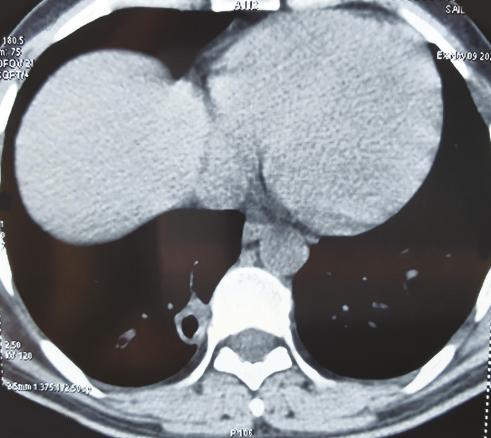

Cet homme de 35 ans, sans antécédents particuliers, avait depuis un mois une toux sèche avec une fièvre, des sueurs nocturnes, une asthénie et un amaigrissement de 10 kg. À l’examen, on notait des conjonctives décolorées, une splénomégalie et des adénopathies sous-mandibulaires. La biologie montrait une pancytopénie, un syndrome inflammatoire biologique, un taux de prothrombine bas (53 %). Sur la tomodensitométrie (TDM) thoracique, on notait un nodule pulmonaire excavé médiobasal droit (fig. 1 ). Des corps de leishmanies intra- et extramacrophagiques étaient trouvés au médullogramme (fig. 2 ). Le patient était traité par antimoniate de méglumine (Glucantime) à raison de 3 g/j pendant vingt jours ; sur la TDM de contrôle cinq mois après la guérison, le nodule pulmonaire s’était densifié (fig. 3 ).